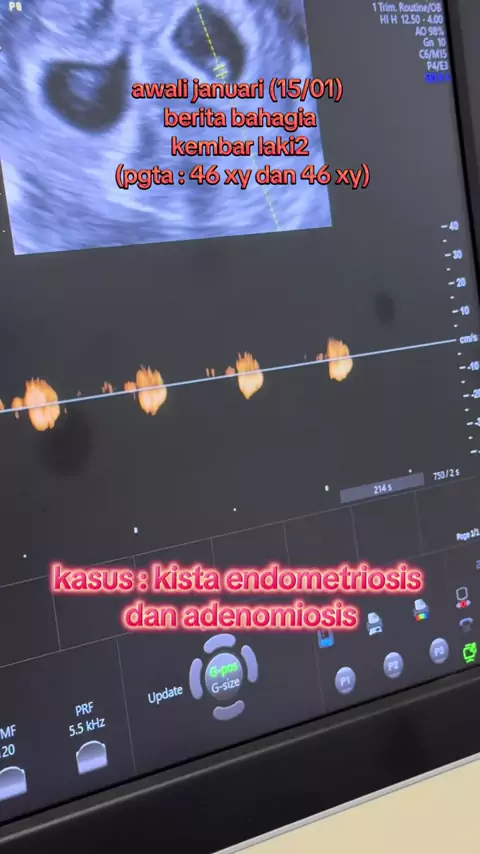

report 06/02-2026 Alhamdulillah setelah pasien ini melewati hari-hari yang berat dan panjang yaitu 2x mengalami operasi luar rahim (kedua tuba diangkat), menjalani program IVF sebelumnya dan gagal, baru datang keklinik kita @klinik_desani kemudian ditemukan adanya PCOS dan Adenomiosis, dilakukan IVF dan embrio yg didapatkan dilakukan PGTA dengan hasil keduanya perempuan (46 XX), transfer embrio beku dengan long protocol, alhamdulillah bisa hamil dan bagus jantungnya.. Alhamdulillah ya Allah @k...